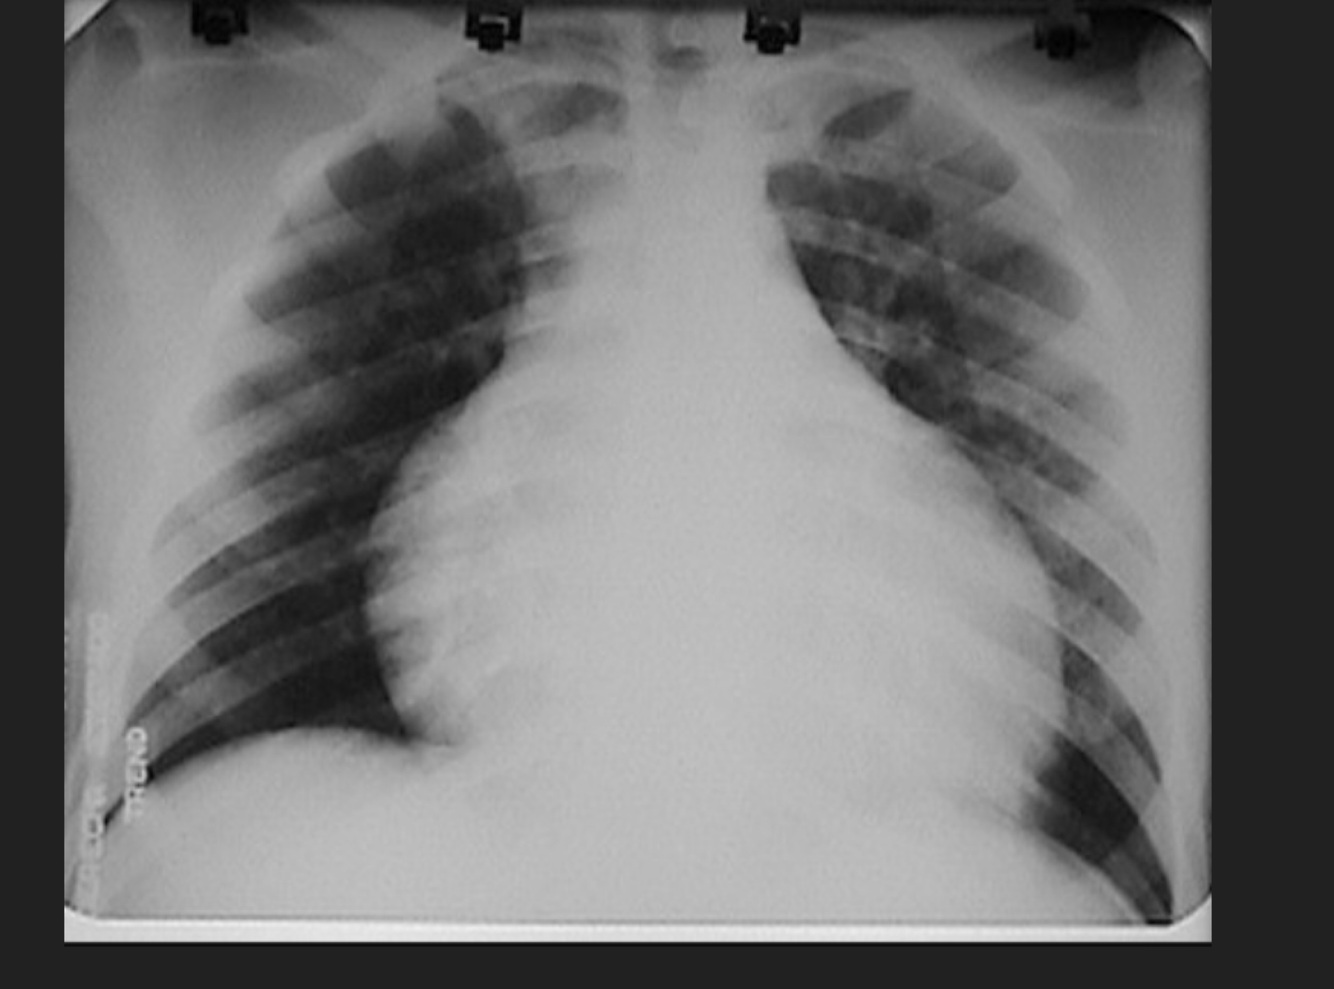

Q

Masculino de 45 años, accidente automovilístico, disnea, dolor en tórax

A

Tórax inestable